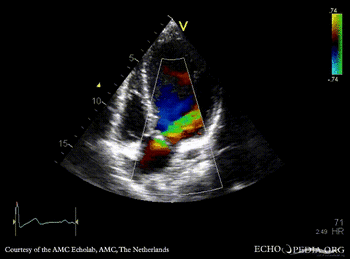

PSAX: bicuspid aortic valve PSAX with Color Doppler: severe aortic regurgitation